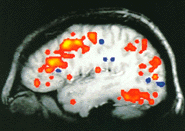

Functional imaging is also now also possible utilizing special metabolic markers and MRI,

and computerized techniques for mathematical processing and visualization of the images. In this way, non-invasive

evaluation of brain function in epilepsy, Parkinson's disease and other brain conditions can be performed with

extraordinary precision and sensitivity.